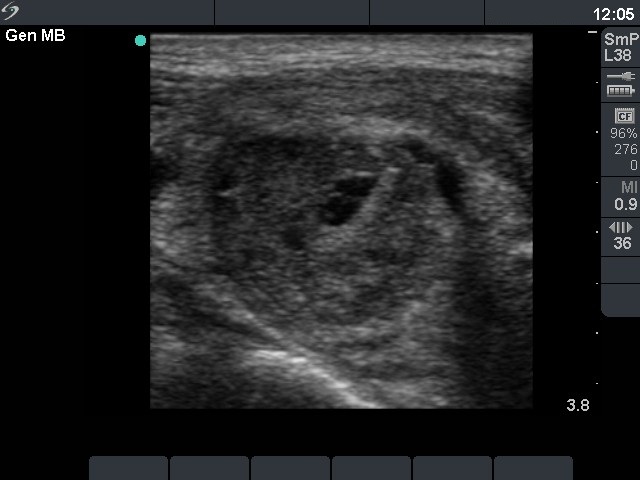

Sclerotherapy and subacute-granulomatous thyroiditis-like reaction after 2nd session (3-5. rows of images):

Instead of repeated surgery, we advised ethanol sclerotherapy. Two sessions of treatment are demonstrated. The day after the second sclerotherapy a painful lump evolved in the right lobe and the patient had fever. We advised steroid therapy which resulted in prompt amelioration of the complaints.